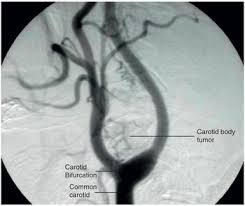

Carotid body tumor excision

Excision of Growths in the blood vessels near carotid arteries, typically benign noncancerous but may affect nearby nerves and blood vessels if they get larger.

Surgery for a carotid body tumor involves removing the tumor and repairing any damage to the carotid artery. A procedure called embolization may sometimes be performed before the operation. The surgical procedures are generally very safe, with good outcomes.

Carotid body tumors are rare, occurring in about 1 in 30,000 people, Carotid body tumors are more common in women